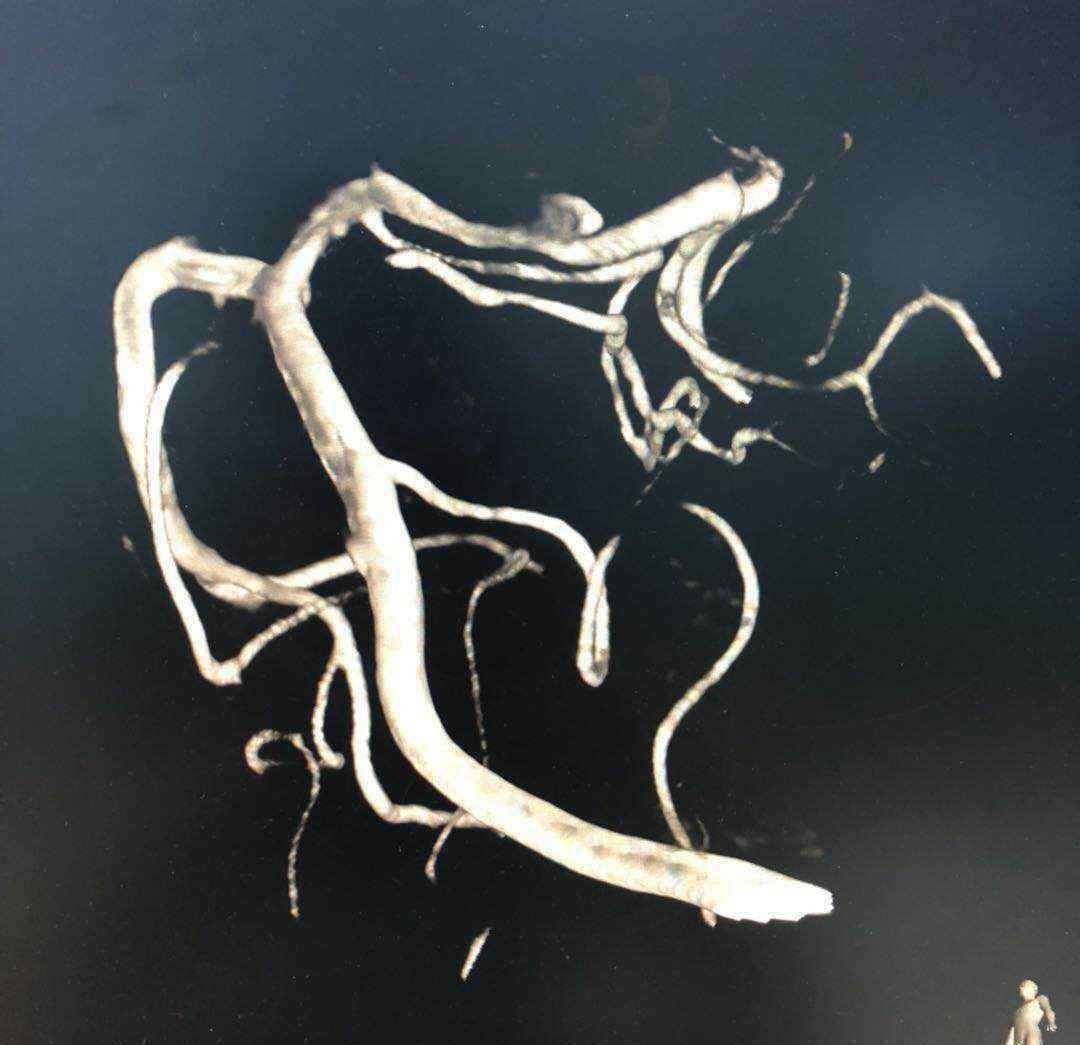

于2019.4.18日行颅内动脉瘤栓塞术

术后患者神清语明,四肢无瘫

1.《魏继光 魏继光,男性,55岁,左侧大脑后动脉动脉瘤。》援引自互联网,旨在传递更多网络信息知识,仅代表作者本人观点,与本网站无关,侵删请联系页脚下方联系方式。